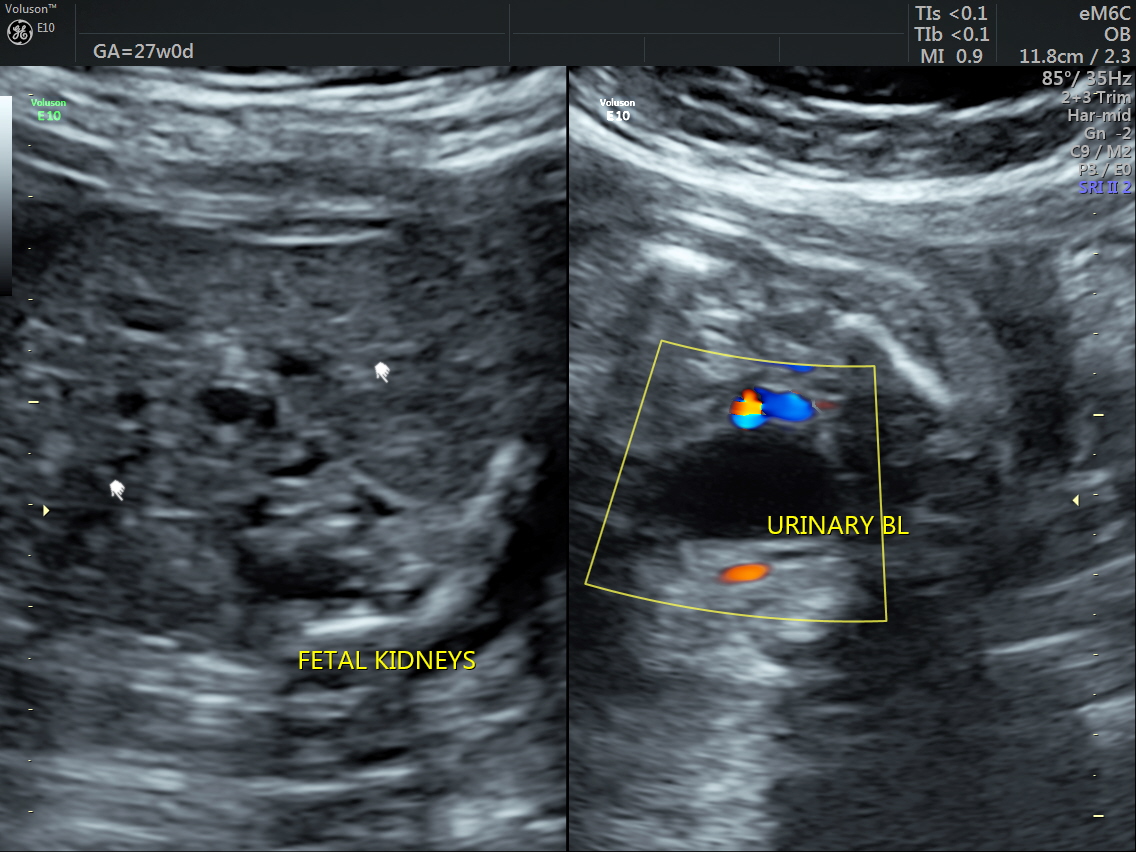

RT AORTIC ARCH_23 Published June 17, 2016 at 1136 × 852 in Rt aortic arch and aberrant left subclavian artery ← Previous Next →